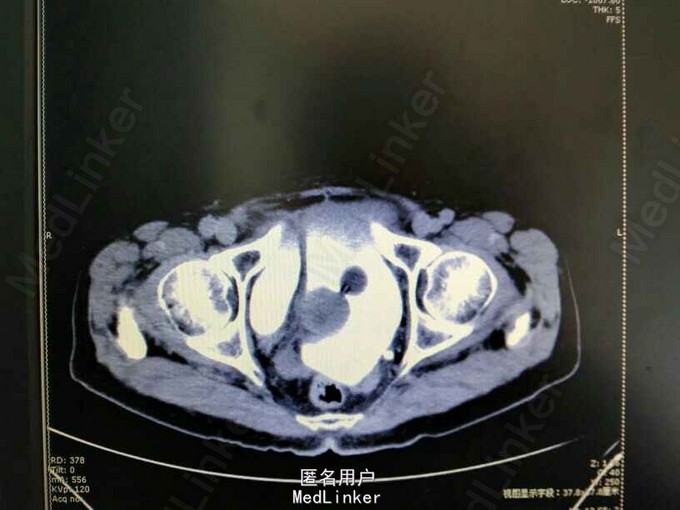

膀胱憩室一例

前列腺增生 膀胱憩室 尿路感染

80岁,男性,因“排尿困难10年,加重伴小便不能自解5小时”入院。既往无高血压、糖尿病等病史。

1.前列腺增生症 尿潴留 膀胱憩室;2.复杂性尿路感染

下一步治疗方案? 处不处理膀胱憩室? 咋样处理膀胱憩室?开放手术?腔镜手术?